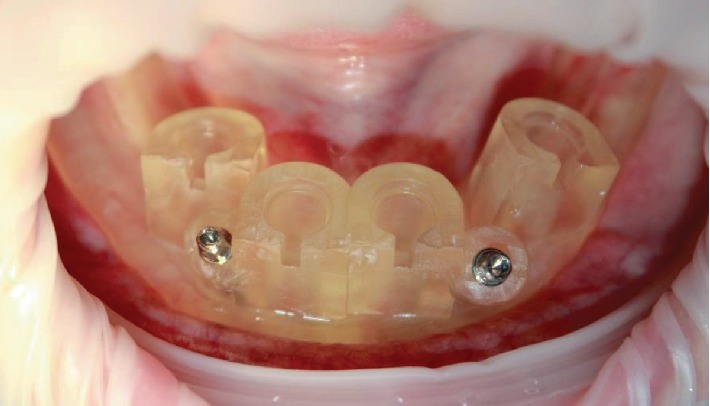

Фиксированный хирургический шаблон.

Хирургический шаблон был установлен на нижнюю челюсть, после чего был помещён силиконовый индекс. Пациентка сжала челюсти, чтобы зафиксировать положение шаблона. Затем были установлены фиксационные штифты, и силиконовый индекс был удалён.

Первое сверление было выполнено через хирургический шаблон с помощью специального трансгингивального сверла типа мукотома для удаления мягких тканей. Поскольку хирургические шаблоны ограничивают охлаждение в процессе сверления, последовательное сверление проводилось на скорости 350 об/мин согласно ранее разработанному протоколу.

Установка имплантатов проводилась через шаблон с помощью специального имплантовода, обеспечивающего точную установку по высоте.

Итоговый крутящий момент при установке составил 40 Н·см.

Однако, с учётом того, что ряд имплантатов был установлен в области резцового канала нижней челюсти, было принято решение ограничиться установкой формирователей десны. Закрытие операционного поля не потребовалось благодаря использованию мукотома.

Формирование десневых абатментов на месте.